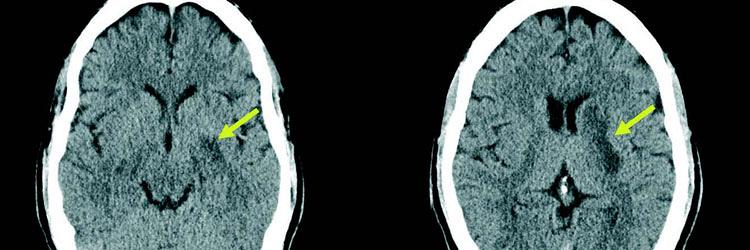

Looptraining na een CVA in de rechterhemisfeer

Als een fysiotherapeut looptraining geeft na een CVA in de rechterhemisfeer, dient hij rekening te houden met een aantal specifieke stoornissen die verband houden met een letsel in de rechterhemisfeer. Vanuit de probleemanalyse en de hulpvraag lijkt het aannemelijk om in een vroeg stadium het lopen te gaan trainen; dit beveelt de KNGF-richtlijn Beroerte ook aan. Bij deze casus blijken echter de problemen met het lopen op de loopband te verergeren terwijl het ‘gewone’ lopen goed gaat. Waarschijnlijk zijn deze problemen terug te voeren op angst en de moeite om nieuwe handelingen uit te voeren. Routinematige activiteiten die meer een beroep doen op de intacte linkerhemisfeer blijken gemakkelijker te gaan, bij deze patiënt het lopen in de duinen. Fysiotherapeuten dienen in hun behandelplan dus rekening te houden met de specifieke uitingsvormen van rechterhemisfeerproblematiek.